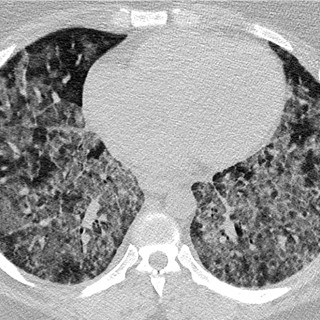

Kronisk transplantat-mot-vert-sykdom er en senkomplikasjon etter allogen stamcelletransplantasjon, og medfører kronisk inflammasjon og fibrose i forskjellige organer på grunn av feil regulering av donors immunceller. Sykdommen kan forekomme i alle organer, men sees hyppigst i hud, øyne, munnhule, gastrointestinaltraktus, genitalia, lunger, muskler, fascier og ledd. Kronisk transplantat-mot-vert-sykdom er assosiert med betydelig sykelighet og dødelighet, og behandling krever tett samarbeid mellom forskjellige deler av spesialisthelsetjenesten. Vi gir i denne artikkelen en klinisk oversikt over...